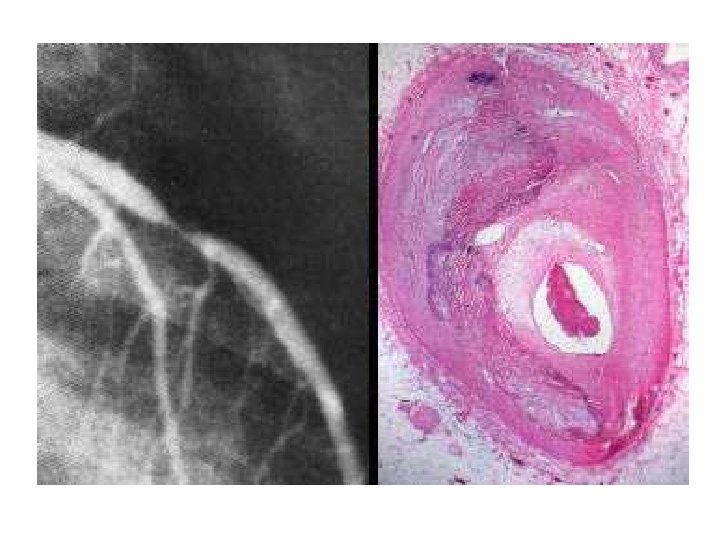

The left frame shows marked narrowing as seen

• The left frame shows marked narrowing as seen by angiography. The right frame shows the histology of the narrowed area. There is marked thickening of the wall due to fibrosis of the intima. This results from coronary atherosclerosis, The red mass in the narrowed lumen is a postmortem clot. • What is the difference between a postmortem clot and a thrombus?

What is the difference between a postmortem clot and a thrombus? • Postmortem clots are not attached to endothelium; they are gelatinous, rubbery, dark red at the ends and yellowish elsewhere. Thrombi are attached to endothelium and are traversed by pale grey fibrin strands that can be seen on cut section; they are more firm but fragile.